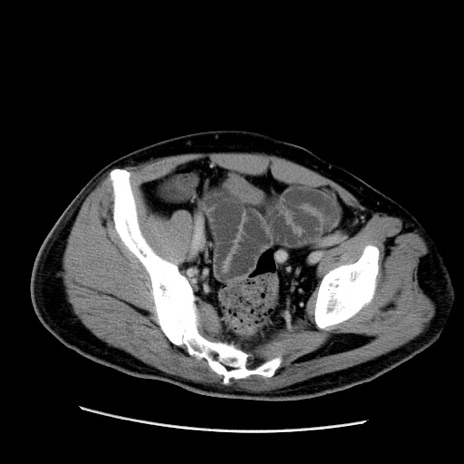

症例22(横断像)

【症例】50歳代男性

【主訴】腹痛

【現病歴】AVMからの被殻出血のため回復期リハ病棟入院中。 本日午後3時頃急に下腹部痛が出現した。

【既往歴】AVM、被殻出血、虫垂炎、高血圧

【身体所見】意識晴明、左半身不全麻痺、会話の理解は良好、36.5°C、腹部:膨隆、全体に板状硬、下腹部正中に圧痛点あり、反跳痛-、筋性防御不明、右下腹部にope scar

【データ】WBC 9400、CRP 0.06